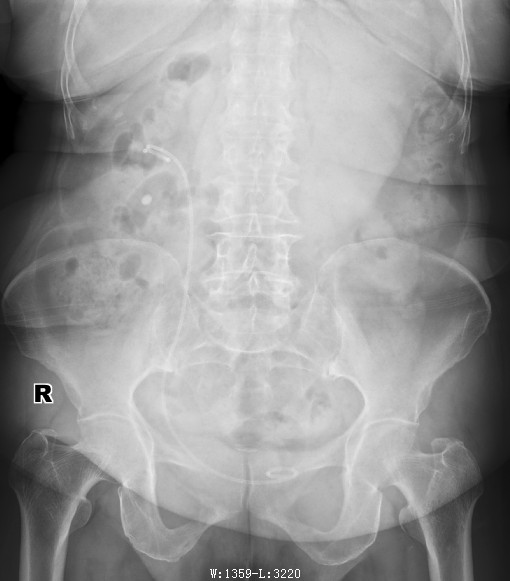

效果基本不错,有极少数残余结石,通过后期活动排石,有可能结石会全部排出体外;术后3-4天出院,极大的解决住院时间长,并术中基本没有创伤;有点很突出;我们再看看今天一例男性患者

通过上图,我们看到了,输尿管软镜技术,很好的解决了以前因为结石小,位置高而不敢做的难题,我院已开展200余例,取得了很好的进展;残石率低于上级医院,我们的宗旨为了患者的一切,全心全意为江陵人民服务,要求尽一切可能减少患者的痛苦及再做手术的可能;